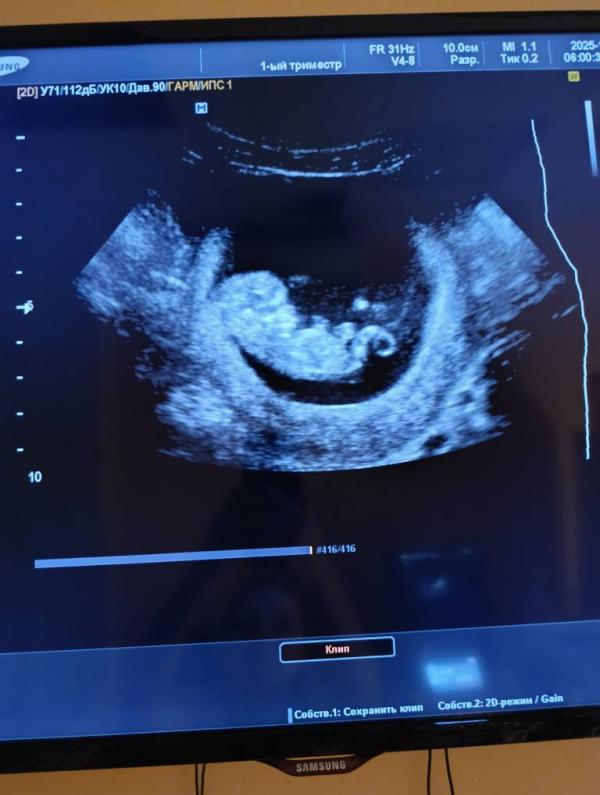

Мой маленький человечек🥹💓

Новая жизнь - это, по истине, чудо.

Ну вообще там они же до определенного момента все с хвостиком 😅 а так может это вообще пуповина так выглядит

Ну тут прям хвостище😁 да и к моему сроку он уже должен "рассосаться")) скорее всего, да, просто снимок так получился. Пуповина или еще что-то)

Меня этот хвостик и смутил, непонятно, что такое😁 надеюсь всё в норме)) Мне узи не делали, это просто на плановом приёме гинеколог глянула, что всё норм, сердце бьётся)

Если приглядеться то это не хвостик, а желточный мешочек маленький ещё остался. Просто прям рядом с ножками на фото получилось 😅